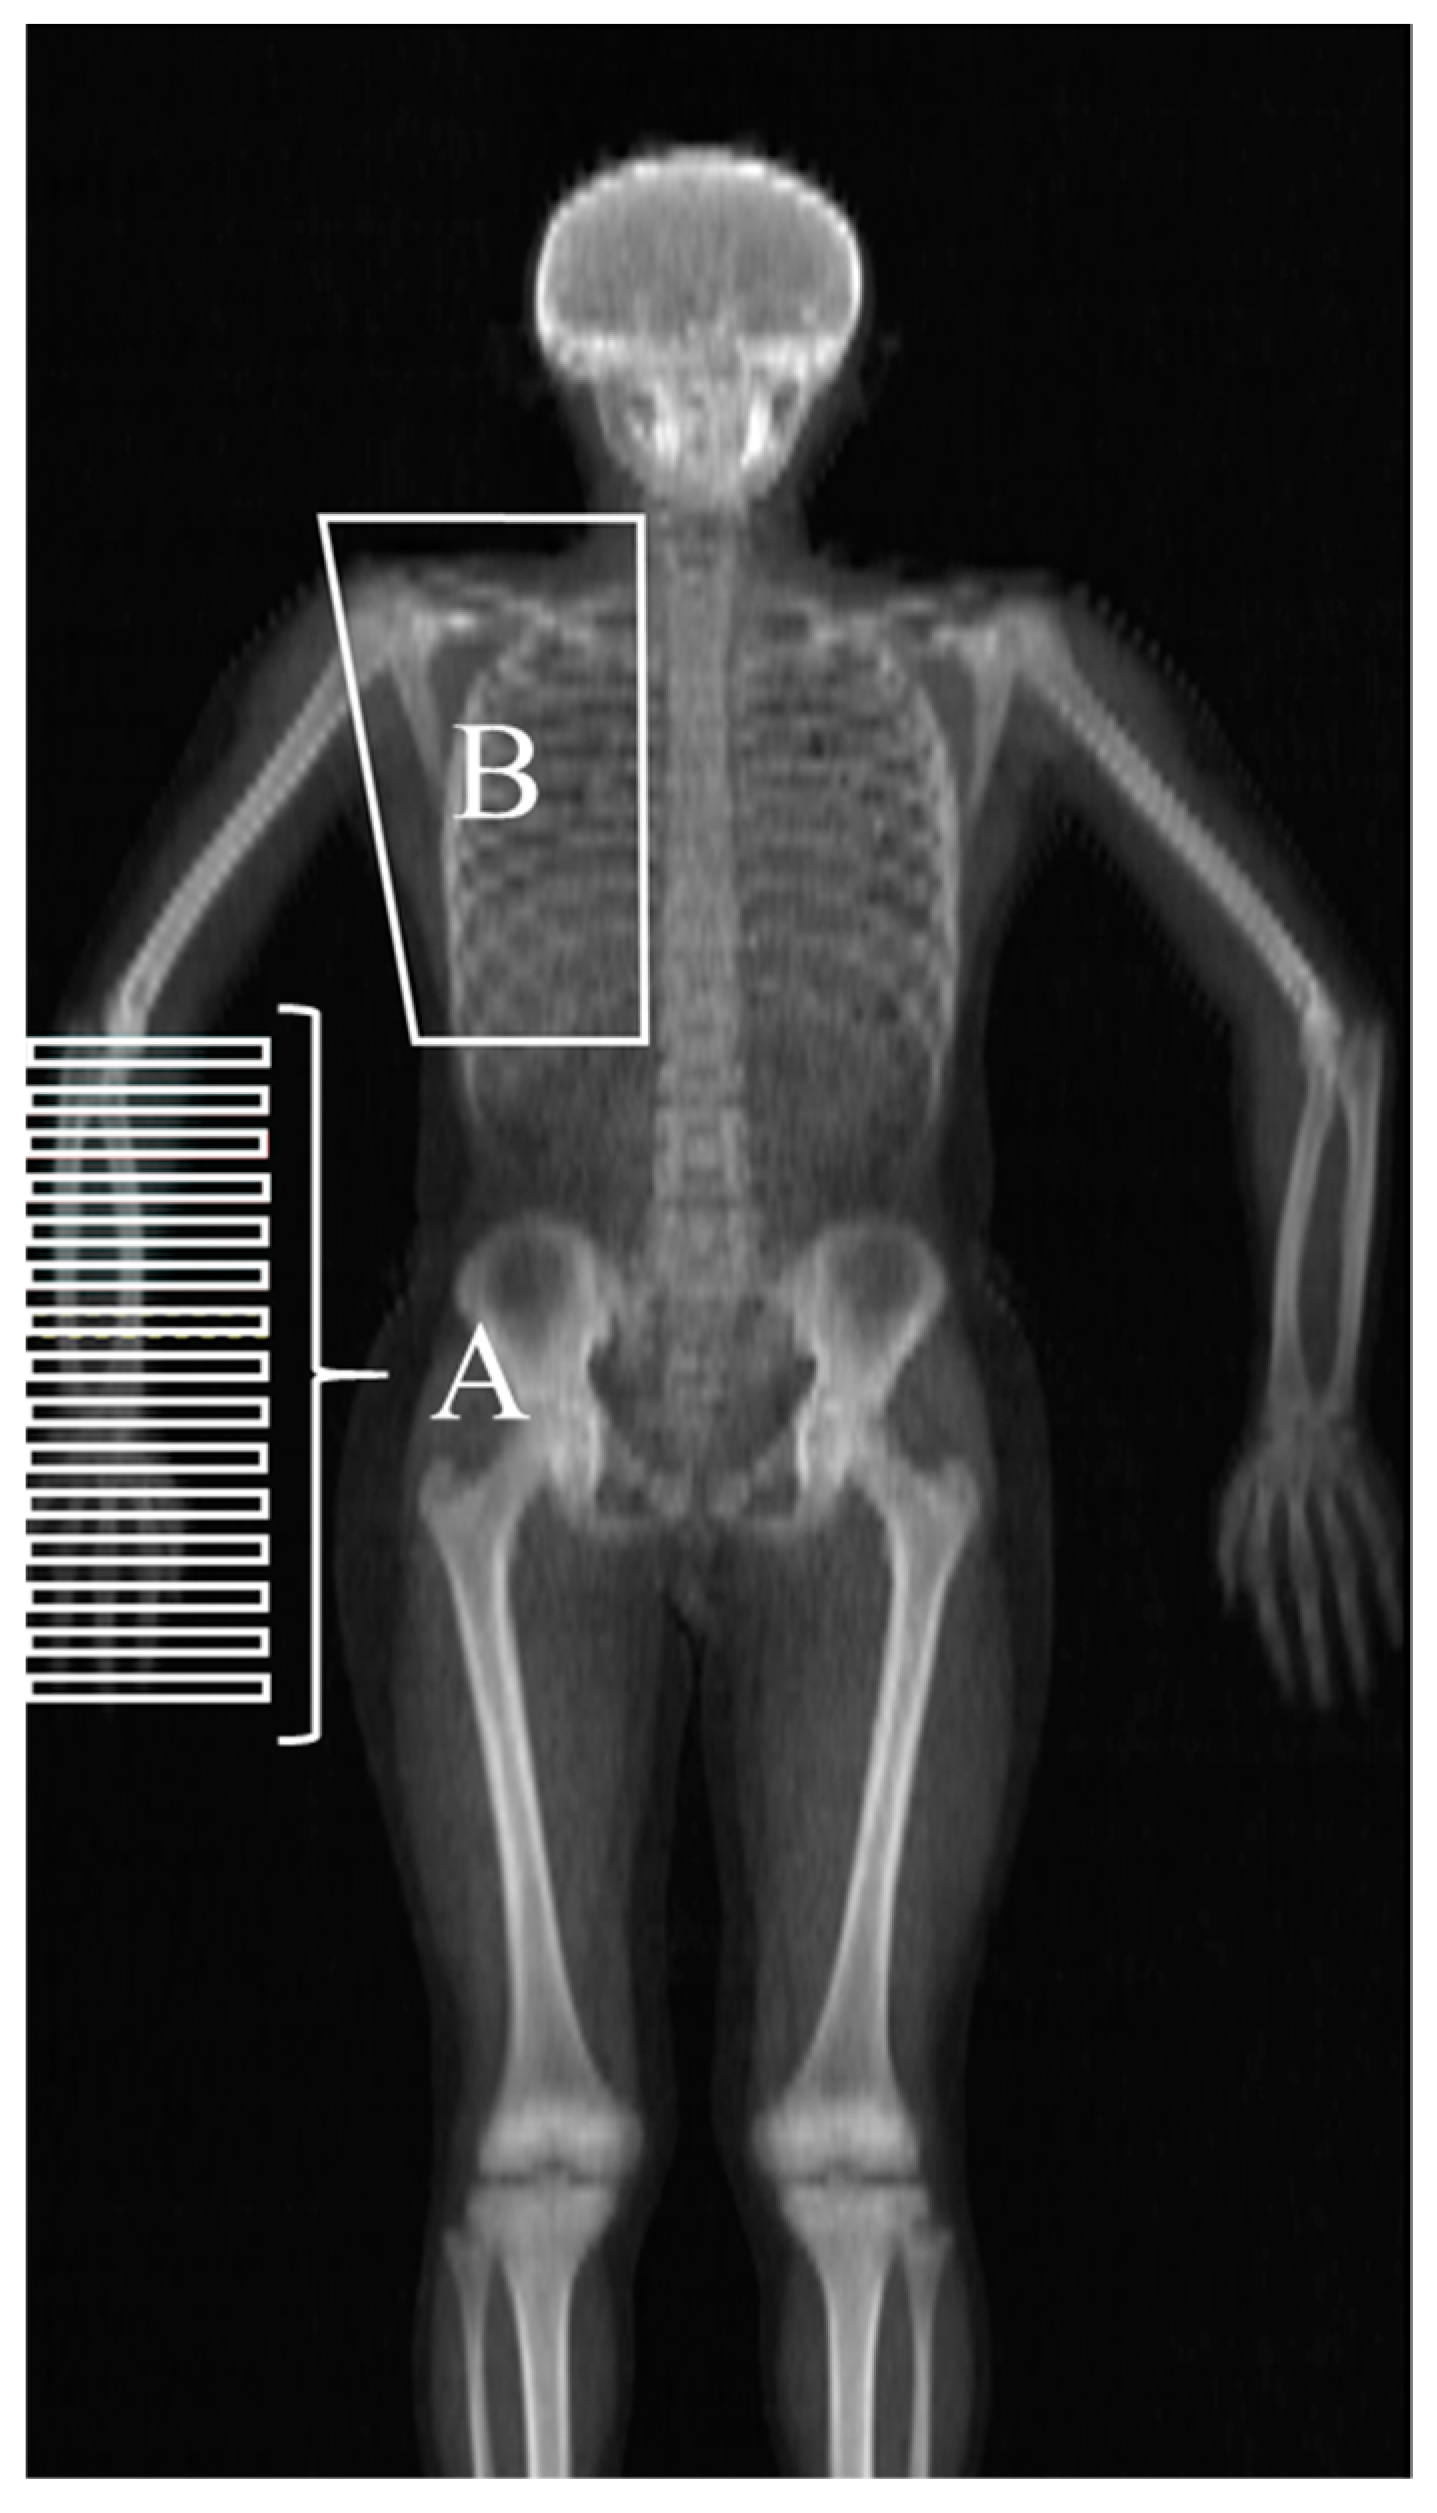

2.2. Procedure and Data Collection